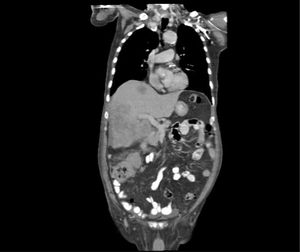

Se reporta el caso de un masculino de 84 años con antecedente de hipertensión arterial sistémica en control. Inició su padecimiento hace tres meses, mostrando principalmente estreñimiento, pérdida del apetito, pérdida ponderal – aproximadamente 12kg –, saciedad temprana, distensión abdominal, astenia y adinamia. Fue tratado sintomáticamente para síndrome de intestino irritable, mostrando nula mejoría, por lo que acudió a atención médica. A su ingreso, se encontró agrandamiento hepático de 2cm por debajo del reborde costal, así como una masa abdominal localizada en el marco colónico derecho, mal definida, móvil y no dolorosa a la palpación. Tras estos hallazgos se solicitaron pruebas complementarias: Ultrasonido hepático y de vías biliares reportó hepatomegalia con parénquima granular y heterogéneo, presencia de nódulos y masas iso e hipoecoicas con características metastásicas, con puntos brillantes sugestivos de microcalcificaciones, así como una masa anecoica multilobulada que comprimía y desplazaba la vesícula biliar. Por otro lado, una tomografía computada con contraste de tórax, abdomen y pelvis confirmó los hallazgos en hígado y reveló un engrosamiento concéntrico y asimétrico de la pared colónica, de entre 15 y 21mm, con calcificaciones puntiformes y una longitud total aproximada de 71mm a nivel del ángulo hepático. Se identificó un ganglio linfático redondeado de 6mm de diámetro, además de múltiples divertículos en colon sigmoides y descendente. Sin evidencia de afectación metastásica en otros órganos (fig. 1). Posteriormente, se realizó una colonoscopia con toma de biopsia, en la que se observó una lesión de aspecto neoproliferativo, dura, ocluyendo toda la luz intestinal y cubierta por exudado fibrinopurulento en la unión del tercio medio y el tercio inferior del colon ascendente. La histopatología de la lesión reportó un adenocarcinoma bien diferenciado y ulcerado de tipo intestinal. Debido a la persistencia de la obstrucción intestinal, se realizó una laparotomía con una hemicolectomía derecha más resección del íleon transverso con anastomosis término-lateral. La pieza obtenida fue enviada a histopatología donde se informó márgenes quirúrgicos negativos, con dos de siete ganglios positivos para metástasis, estableciendo así el diagnóstico final de carcinoma con componente sarcomatoide, tumor de alto grado (G4), compuesto por elementos mucinosos (60%), intestinales (20%), micropapilares (5%) y sarcomatoides (15%). La neoplasia infiltraba la submucosa, la muscular propia y los tejidos pericolónicos, sin perforación del peritoneo visceral, pero con invasión linfovascular (fig. 2A-D). Tras una adecuada evolución posquirúrgica, el paciente fue referido a consulta externa de oncología médica para valorar tratamiento adyuvante, dada la irresecabilidad de las metástasis hepáticas.